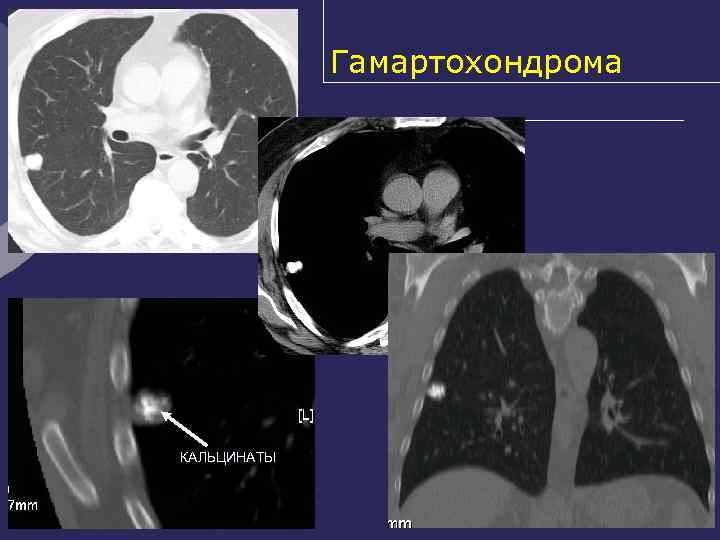

Гамартохондрома Ø Нарушение развития мезо- и энтодермы Ø Макроскопически – образование шаровидной формы, эластической консистенции, с мелкобугристой поверхностью (дольчатое строение) Ø Капсула отсутствует, есть ложе Ø Микроскопически: между хрящевыми элементами включения миксоидной, волокнистой соединительной, мышечной, жировой, сосудистой ткани

Гамартохондрома В отличие от туберкуломы – Ø значительно чаще находится в правом легком (почти в 2/3 случаев) Ø преимущественно (у 75% больных) в 3 -м, 4 -м, 5 -м, 7 - м и 8 -м сегментах легкого Ø Располагается - в периферических отделах и вблизи корней легких, иногда субплеврально, по ходу междолевой плевры

Ретгенологические признаки гамартохондромы Ø Правильная форма Ø Четкие гладкие или волнистые контуры Ø Средняя интенсивность Ø Включения извести (глыбки, слоистость, инкрустации) Ø Окружающая легочная ткань не изменена Ø Бронхи, сосуды огибают образование

Гамартохондрома КАЛЬЦИНАТЫ